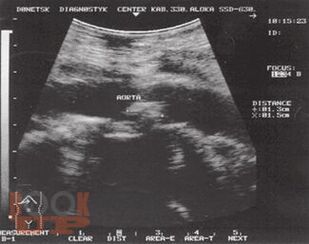

Монография является пятой и заключительной книгой серии «Хроническая абдоминальная боль». Автор представила основные причины боли при заболеваниях других органов и систем, которые могут проявляться абдоминальной болью. Особое внимание уделено патогенезу, клинической характеристике и дифференциальной диагностике болевого синдрома, а также лечению.